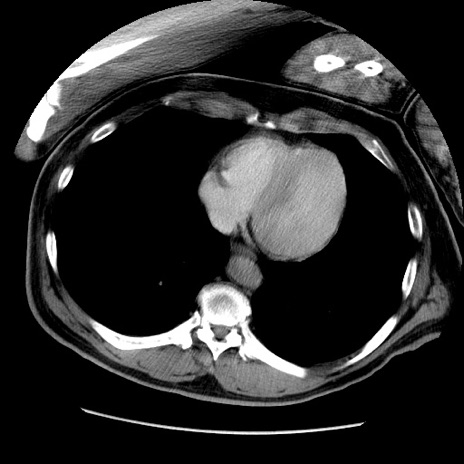

症例22(横断像)

【症例】50歳代男性

【主訴】腹痛

【現病歴】AVMからの被殻出血のため回復期リハ病棟入院中。 本日午後3時頃急に下腹部痛が出現した。

【既往歴】AVM、被殻出血、虫垂炎、高血圧

【身体所見】意識晴明、左半身不全麻痺、会話の理解は良好、36.5°C、腹部:膨隆、全体に板状硬、下腹部正中に圧痛点あり、反跳痛-、筋性防御不明、右下腹部にope scar

【データ】WBC 9400、CRP 0.06